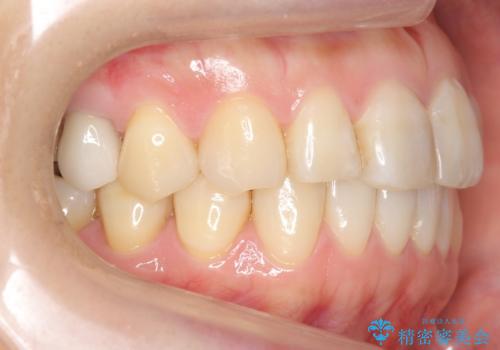

ご希望のマウスピース矯正で歯並びが綺麗になり、大変喜んで頂けました。

食事の度のマウスピース着脱や歯を磨いてからの装着がお仕事上大変なようでしたが、

治療後には笑うと見えて気になっていた銀歯も白くなり、より一層素敵な笑顔を見せて下さいました。

ホワイトニング予定のため、セラミッククラウンの色は隣在歯よりやや白めにオーダーしました。

クラウンの種類:オールセラミッククラウン エコノミー(e-max press Cr)

インレーの種類:e-max press セラミックインレー